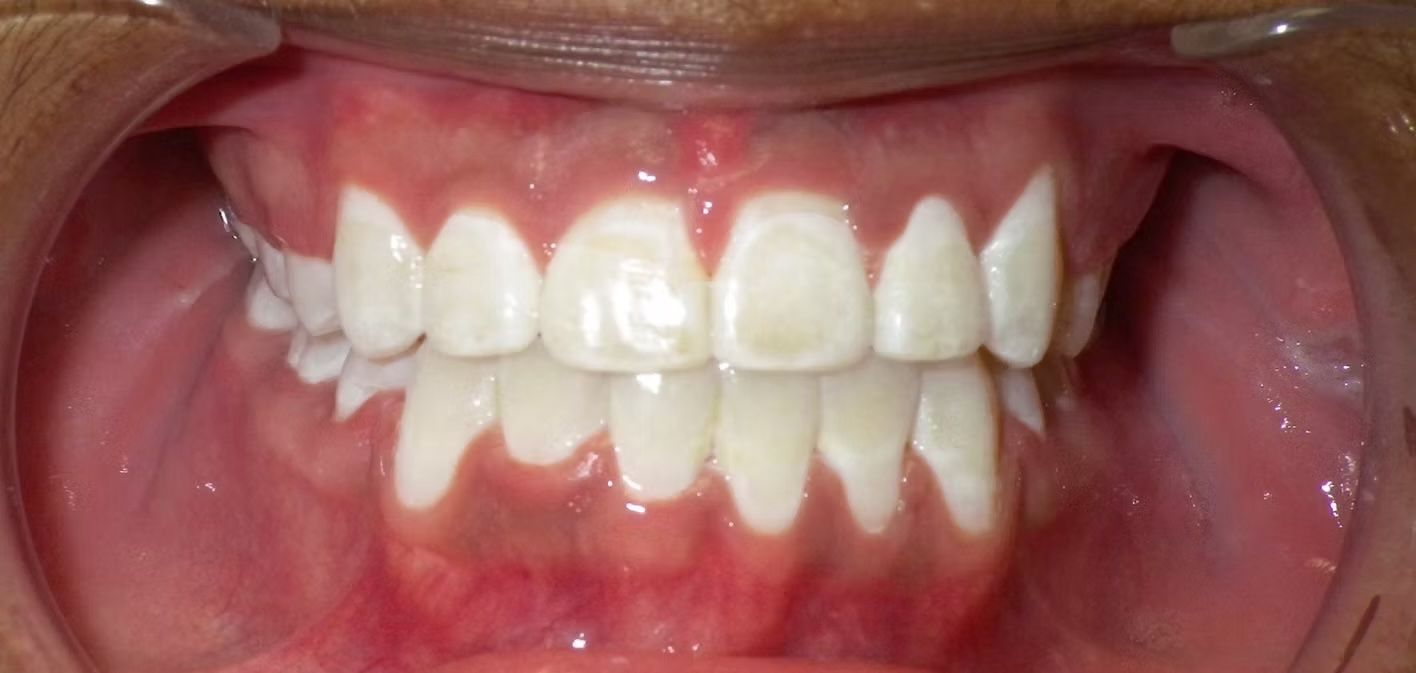

AMBER

Amber, began treatment with Dr. Bret because she didn't like that her front teeth overlapped each other. She had narrow top and bottom dental arches with severe crowding of her upper and lower teeth. She was treated with braces on the upper and lower teeth, and we used the braces to widen the smile. What a change!